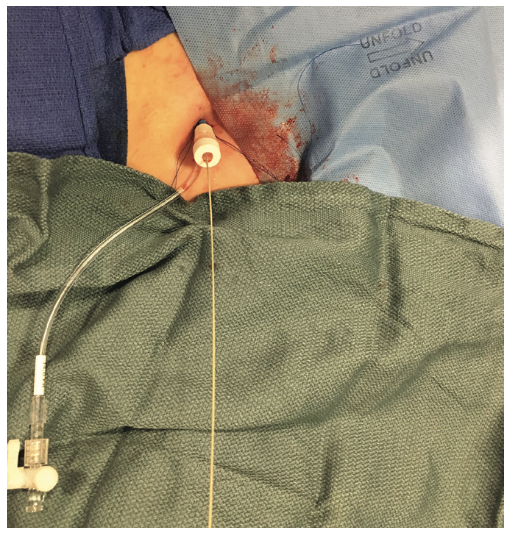

The right groin was accessed using fluoroscopic guidance. A micropuncture sheath was placed and upsized to a 7 French, 45 cm Destination sheath (Terumo) in the right groin. We accessed the right radial, but could not get good flow. Therefore, we ended up using the ulnar artery with ultrasound guidance and placed a Terumo 5/6 Slender sheath in the ulnar artery. We proceeded to access the left axillary artery. We placed a Judkins right (JR)4 catheter in the left subclavian and did a selective angiogram, documenting the location of the thoracoacromial artery and circumflex humeral (Figure 4); then using a Chiba biopsy needle (Cook), accessed the axillary artery and placed a 5-French 30 cm sheath (Cook)(Figure 5). We used the 15 cm biopsy needle to allow us a shallow angle of approach with the patient’s body habitus and to avoid “kinking” the sheath. We then switched out for the Lunderquist wire (Cook Medical), placed an 8 Fr sheath, and performed a pre-close using two Perclose devices (Abbott Vascular) (Figure 6).

- If prolonged hemodynamic support is needed, the Impella sheath should be sutured and secured before the patient leaves the cath lab. In regard to the Perclose sutures, we recommend clamping the sutures with a hemostat and wrapping them with a sterile towel covered with sterile Tegaderm. The towels are then stuck to the chest wall1 (Figure 24).